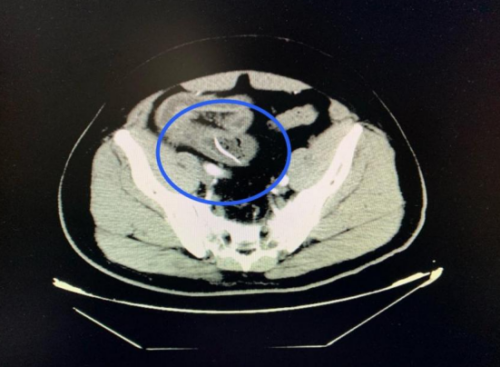

急诊医学科就诊。医生详细询问病情并进行体格检查后,立即安排了腹部 CT 扫描。CT结果显示:回肠高密度影,考虑尖锐异物并小肠穿孔、腹膜炎。结合阳宇军三天前吃甲鱼的经历,医生高度怀疑是误吞甲鱼骨导致了肠穿孔。

CT扫描可见一尖锐的鱼刺状异物